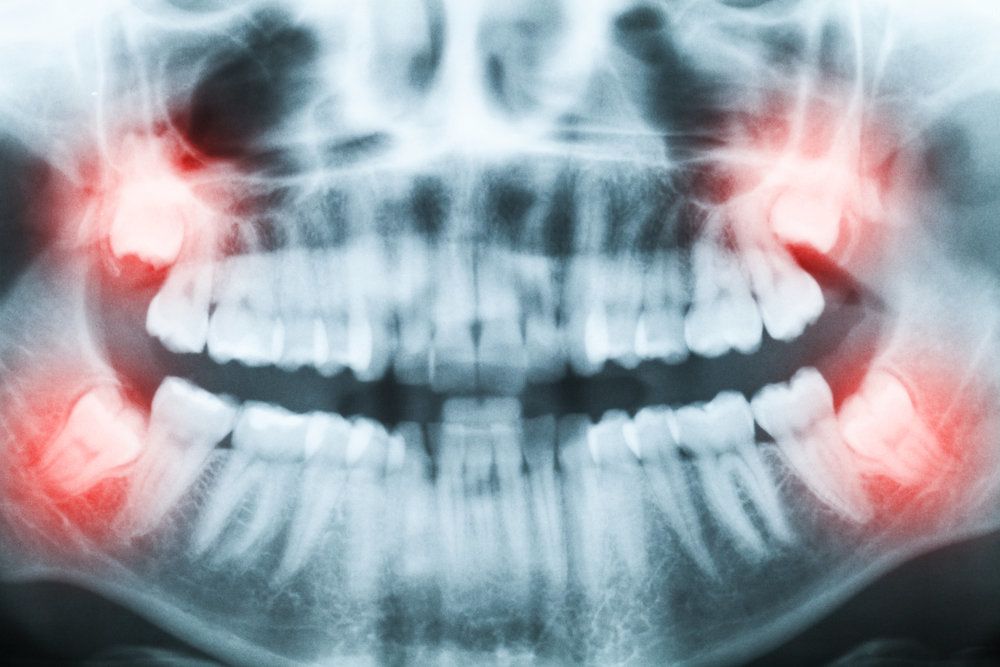

Dr. Berbari will perform a routine examination with a panoramic x-ray to determine if your wisdom teeth will need to be removed. If there are signs of impaction or if the wisdom teeth appear to be growing too close to the adjacent teeth, we can schedule your surgery. The removal procedure can typically be completed in about one hour, and most patients will require two to three days of rest following the appointment. Dr. Berbari will let you know if there are any special precautions for your case, such as fasting, but most patients do not need to take any preparatory measures.